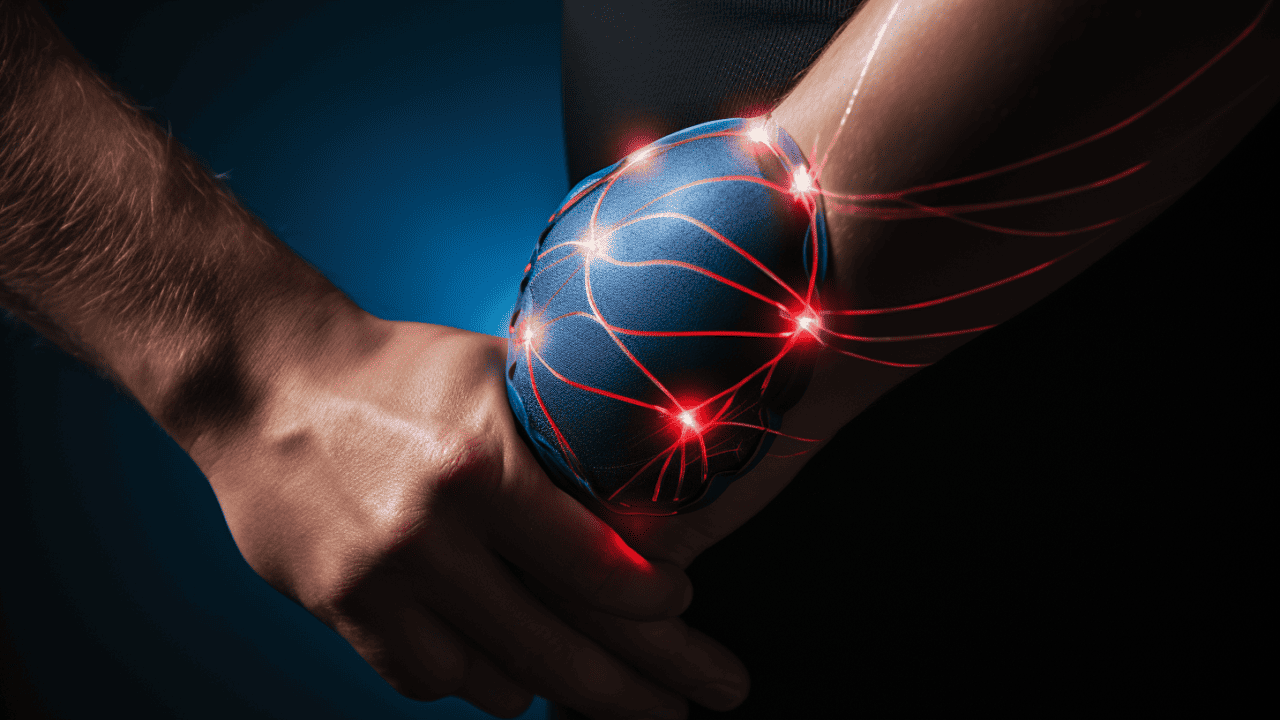

HealthcareManaging Pain With TENS Machines: Exploring The Benefits And Best Practices

Transcutaneous Electrical Nerve Stimulation (TENS) is a pain treatment method that uses electrical currents through the skin. These target specific nerves, temporarily blocking pain signals from reaching the brain. The process provides relief and stimulates the body’s natural healing processes. A TENS machine accomplishes this through a small, battery-powered device connected to wires and electrodes. These components work in unison, delivering low-voltage electrical impulses to stimulate the nerves and disrupt normal pain signals. Additionally, TENS...